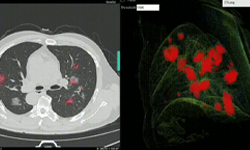

This work encompassed two models that were used in series to come up with the COVID final classification model. The first model was a segmentation model that was used to define the lung regions which were subsequently used by the classification model. Initially, they developed two classification models — one utilizing the entire lung region with fixed input size (full 3D), and one utilizing average score of multiple regions within each lung at fixed image resolution (hybrid 3D).

Training converged at highest validation accuracy of 92.4% and 91.7% for hybrid 3D and full 3D classification models, respectively, for the task determining COVID-19 vs. other conditions. The validation accuracy in an unseen independent test set was observed with the 3D classification model (93.9%), with resultant probability of COVID-19 disease demonstrating 0.941 AUC. This was the model that was selected at the end, and published on NVIDIA NGC.